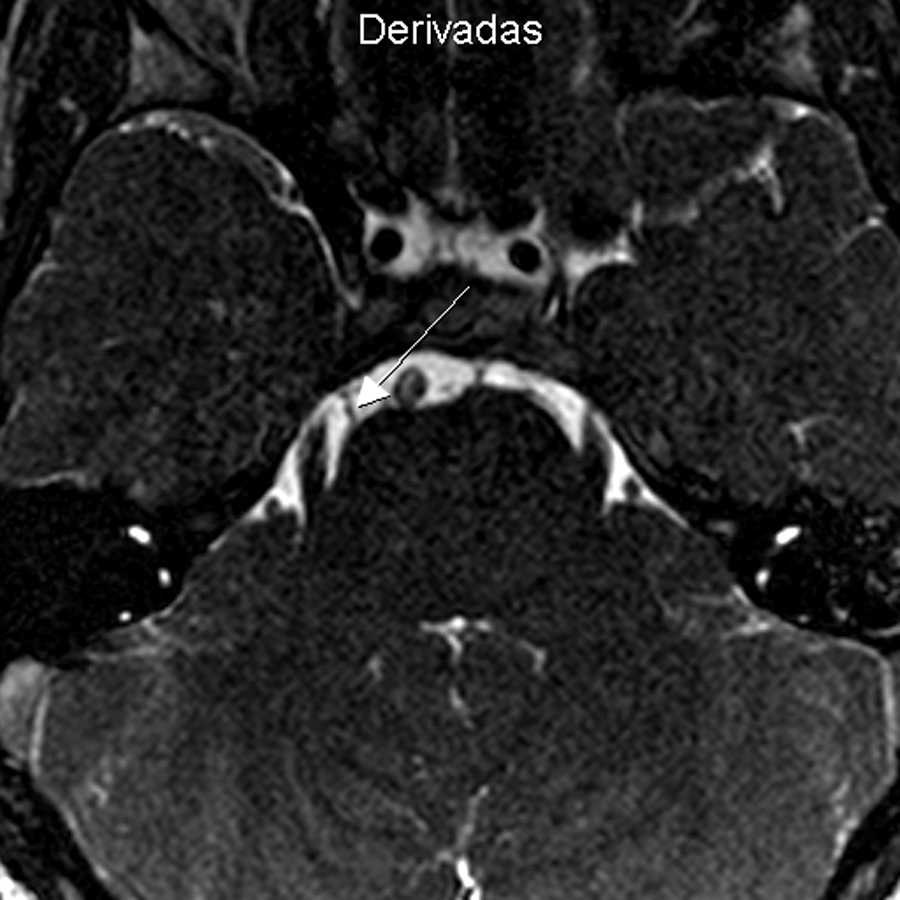

Se solicitó una resonancia magnética (RM) de ambas órbitas con cortes finos en el tronco encefálico, focalizados en la cisterna prepontina, sin gadolinio. En las órbitas no se encontraron alteraciones (no se muestra la imagen), mientras que a nivel de la cisterna pontina en secuencias balanced fast field echo(BFFE) y en ponderación T2 drive tridimensional (3 D) con reconstrucción multiplanar se objetivó la ausencia del sexto nervio craneal izquierdo (fig. 1).

Una correcta anamnesis, exploración clínica y estudios por imágenes como la RM permiten arribar al diagnóstico correcto3,4. La no visualización del sexto par en la RM confirma el diagnóstico de SRD, especialmente con secuencias ponderadas en T2 y 3D2–4,7. El contraste endovenoso (gadolinio) no es de utilidad.